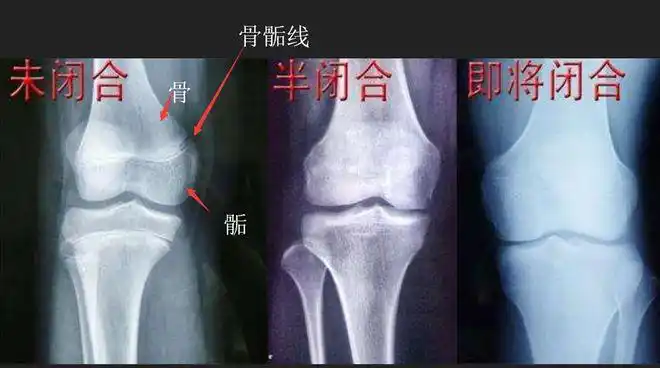

所谓的骨骺线,就是孩子未成年时,关节处的那部分透明的软骨组织,当

家长放心,只要骨骺线未闭合,孩子的身高都还有增长的空间!

这是最关键,一切长高都在骨骺线未闭合的基础之上.

骺板提早消失,骨不能长长.